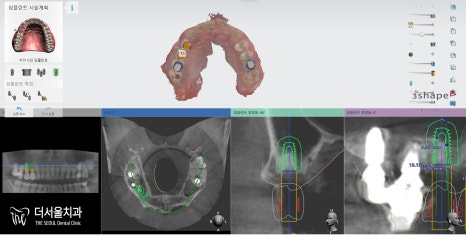

자, 이렇게 초진을 끝낸 뒤에

컴퓨터 사전 진단 프로그램으로

정밀 진단을 했습니다.

그 결과 시뮬레이션에서도

상악동 골이식 및 거상술을 해야 된다는

내용을 볼 수 있습니다.

‘Sinus lifting & GBR’은 필수입니다.